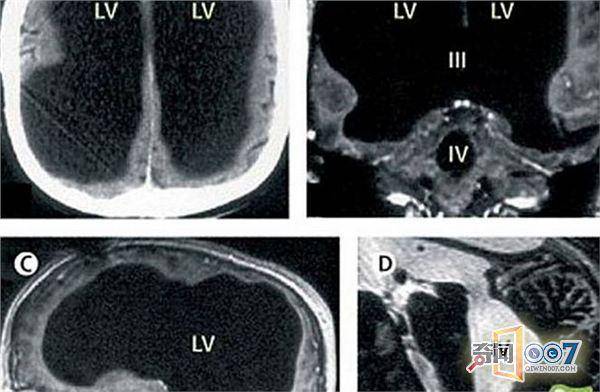

法国男子,因为脚部疼痛去医院检查。医生却在检验时发现一个惊人的真相,男子的大脑只剩下10%。

男子的大脑少了近80%,追踪他的既往病史,原来这名男子在6岁时患上了“水脑症”,当时医生排出了他脑袋里的积水。接下来的几十年里,积水的情况复发并凝结,摧毁脑部并占据原本脑袋的空间。

很难想象这名两个孩子的父亲是怎样正常生活的,他的IQ值测试只比平均水平少一点,而且他还是一名公务员。

那为什么出了这么大问题,男子仍能正常生活。医学家指出“大脑的可塑性”,人脑可以重新整理神经通道,让没有消失的脑袋接下原本其他区域的任务。听起来很神奇吧,大家一定要多多注意身体哦。